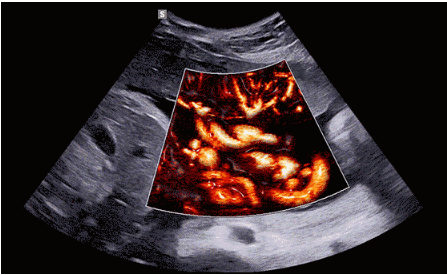

CrystalLive?是三星最新的超聲成像引擎,同時(shí)增強(qiáng)了2D圖像處理能力、3D渲染能力和彩色信號(hào)處理能力,能夠在復(fù)雜情況下提供出色的圖像性能,具備檢測(cè)外周血管、微循環(huán)血流的能力。

2D成像方面,Hera i10集成了包括ShadowHDR?、HQ-Vision?、ClearVision等多項(xiàng)具有三星“血統(tǒng)”的技術(shù),加強(qiáng)了圖像的陰影抑制、減少偽影、緩和模糊區(qū)。